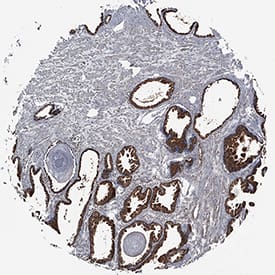

TL1A/TNFSF15 antibody in Human Prostate Cancer Tissue by Immunohistochemistry (IHC-P).

TL1A/TNFSF15 in Human Prostate Cancer Tissue.

TL1A/TNFSF15 was detected in immersion fixed paraffin-embedded sections of human prostate cancer tissue using Rabbit Anti-Human TL1A/TNFSF15 Monoclonal Antibody (Catalog # MAB74421) at 0.3 µg/mL for 1 hour at room temperature followed by incubation with the Anti-Mouse IgG VisUCyte™ HRP Polymer Antibody (Catalog # VC001). Tissue was stained using DAB (brown) and counterstained with hematoxylin (blue). Specific staining was localized to cytoplasm of epithelial cells. View our protocol for IHC Staining with VisUCyte HRP Polymer Detection Reagents.